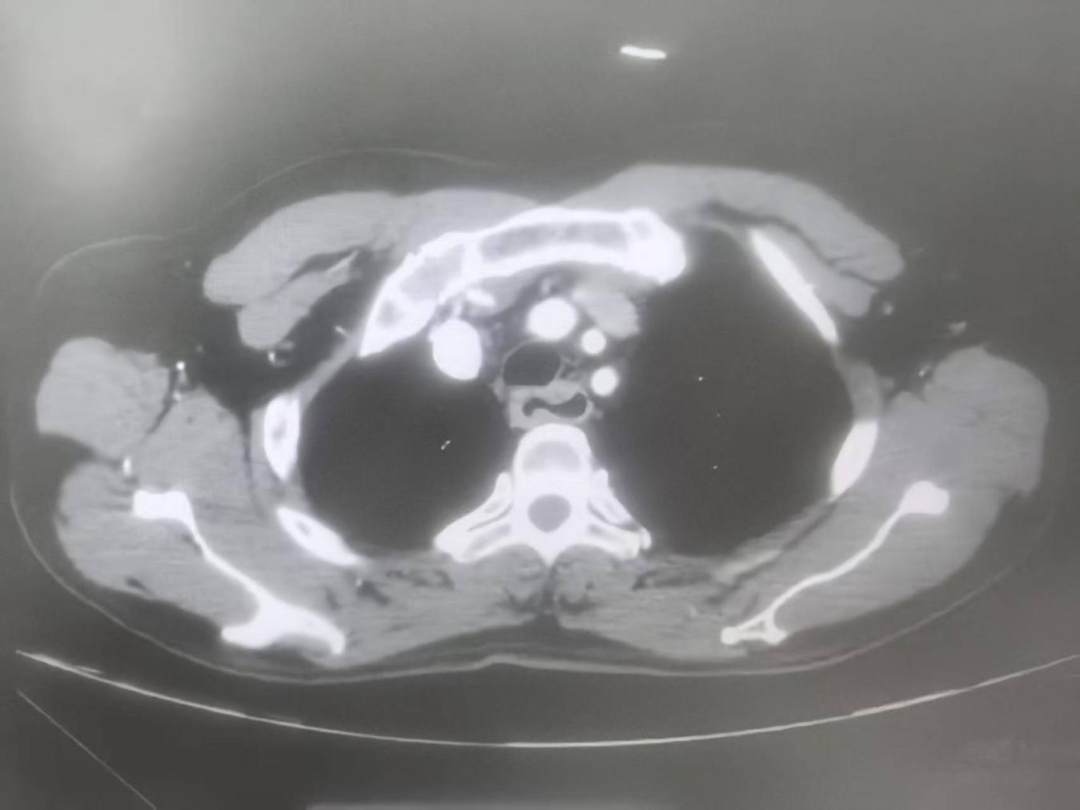

心胸外科副主任、主任医师王明智,主治医师刘炬博士团队接到会诊后,为陈阿公进行全面检查。胃镜提示:肿瘤位于食管开口处,厚11mm,突破食管外层,已经环绕食管3/4周,周围多发肿大淋巴结;CT提示:食管高位肿瘤,48mm*18mm*16mm,与支气管后壁分界不清,周围多发淋巴结;PET-CT提示:2-4胸椎水平食管上段食管癌,右下颈气管旁、右上气管旁淋巴结疑转移。综合考虑局部晚期、高位、食管恶性肿瘤,直接进行手术的风险及难度都很大,医生建议实施新辅助治疗后再进行手术。但这样的治疗方式,让家属们陷入两难境地。

△检查结果